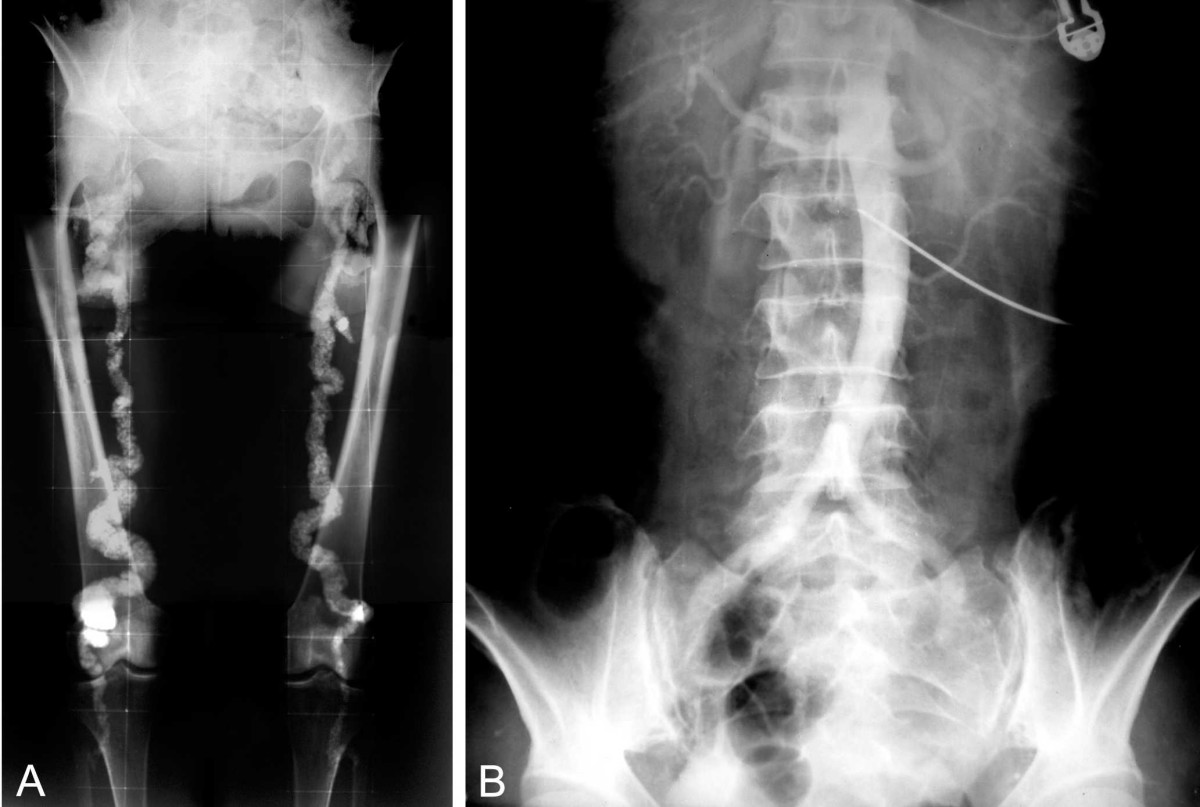

28. 47-y/o man has hypertension in the upper extremities and weak pulses in the lower extremities (Brachial-femoral delay). Why might he have rib notching on X-ray and what complications is he at increased risk for?

Explanation

The correct answer explains the relationship between coarctation of the aorta, rib notching, and the potential complications the patient is at increased risk for.